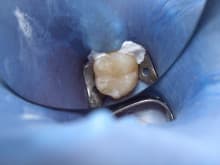

左下大臼歯の虫歯に

ハイブリットセラミックによる

ダイレクトボンディング治療を行った症例についてご紹介します。

治療途中です。

マイクロスコープを使用し

健全歯質はできる限り保存しました。

唾液や細菌の感染を防ぐため

ラバーをかけて治療しています。